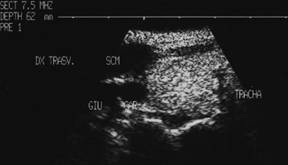

Ecostrutura omogena, normoecogena. Dimensiuni normale.

Se urmaresc rapoartele cu carotida, jugulara, muschii, traheea, esofagul.